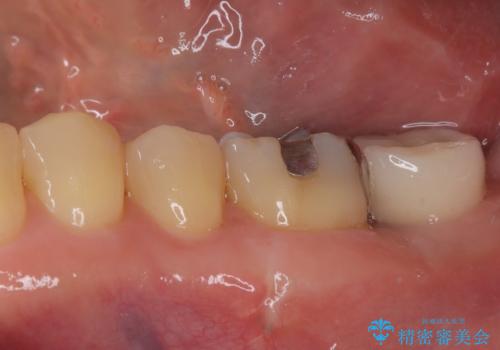

上顎の奥歯は、左右ともに外側に転位しており、特に右上はむし歯の範囲が広く、根管治療も必要な状態でした。

左下の奥歯は状態が非常に悪く、保存は困難と判断されたため、インプラントによる補綴治療が必要でした。

上顎左右の歯をアンカースクリューを用いた部分矯正により位置を修正し、オールセラミッククラウンにて補綴治療を行うこととしました。